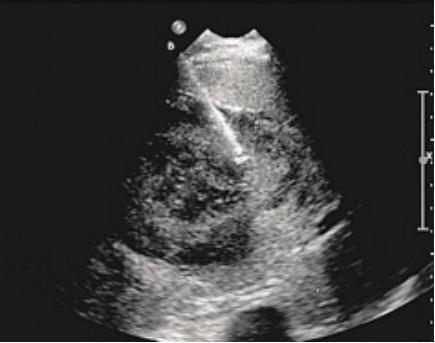

B超引导下肝肿物消融治疗

在实时超声或者CT引导下将消融针穿刺至病灶,通过消融针快速升温,利用高温将肿瘤组织“烧死”,具有微创、“不开刀”等优势,使病灶得到根治性的治疗,如肝脏、肺部、乳腺肿瘤等脏器的消融治疗。